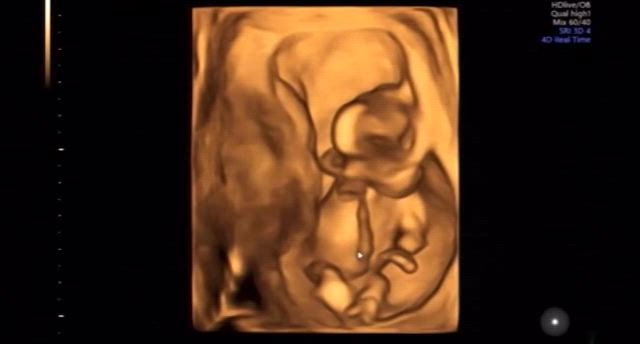

16w6d 妊婦検診♥性別分かりました

【妊娠16週逆子】原因と治し方を助産師さんに相談